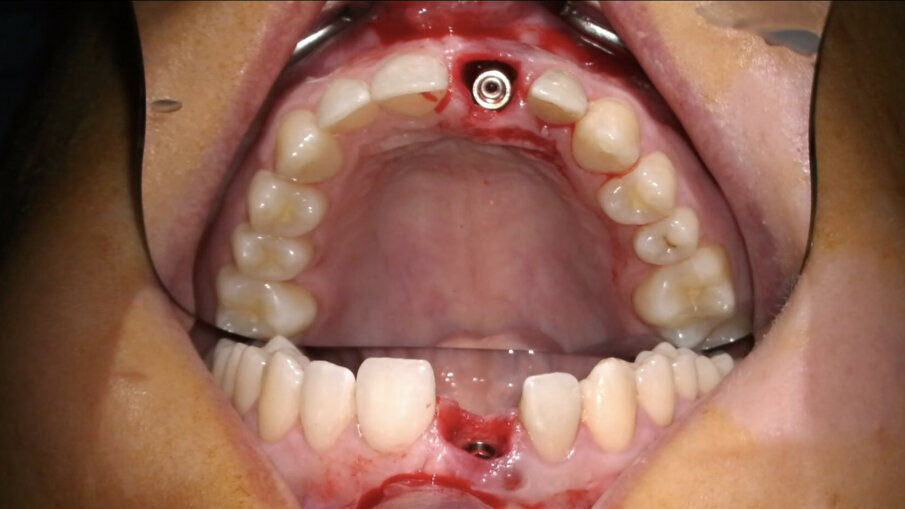

Non vanno eseguite incisioni di scarico in quanto non sono necessarie (Fig. 13). Diversamente, nei casi di edentulia parziale frontale deve essere eseguita un’incisione vestibolare (Fig. 14) a partenza intra-sulculare dai denti adiacenti. Come noto, tale incisione non deve coinvolgere la parte coronale delle papille: l’interessamento dei picchi ossei, infatti, porterebbe inevitabilmente alla perdita di 1-1,5 mm di osso con compromissione dell’estetica finale. In entrambi i casi, al fine di posizionare una matrice in collagene, verrà eseguita un’incisione a spessore parziale creando una piccola tasca mucosa corrispondente alla porzione buccale della zona trattata (Fig. 15).

- Posizionamento implantare

L’impianto (XIVE – Dentsply Sirona) è stato posizionato centralmente con un’inclinazione palatale al fine di evitare che il foro di accesso della vite cadesse sul margine incisale del provvisorio o, ancor peggio, sulla sua superficie vestibolare. Il gap osseo vestibolare è stato riempito con Geistlich Bio-Oss (Geistlich Pharma) (Figg. 16-19).

Fig. 13_Alveolo integro e tessuti molli non incisi.

Fig. 16_Inserimento dell’impianto Xive FX 3.8.

Fig. 17_Posizione corretta dell’impianto post-estrattivo.